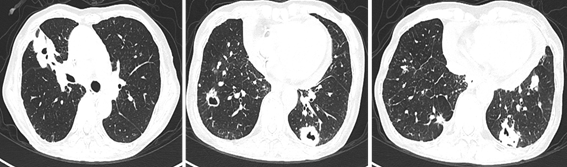

2020.6 胸部双源增强CT:双肺多发大小不等肿块,大者约39*40mm,位于右肺中叶,增强扫描边缘强化。纵隔内见肿大的淋巴结。

2020.11 胸部双源增强CT:双肺多发大小不等肿块,大者约29*52mm,位于右肺中叶,增强扫描边缘强化,部分病灶内见空洞,右肺中叶不张,右肺中叶支气管闭塞。双肺散在条索灶。右肺上叶间质改变。

患者为老年男性,发现乙状结肠癌同时性肝转移。因不全肠梗阻行原发灶根治术。术后根据病理及基因检测结果指导晚期一线FOLFIRI联合西妥昔单抗姑息治疗。肝脏转移灶控制可,进一步行肝转移病灶切除。达影像学无瘤状态NED。随访10个月后出现新发肝脏病灶,考虑PD。予以二线mFOLFOX6方案化疗十程后拒绝进一步治疗。7个月后出现多发肺转移,考虑PD。三线治疗予以瑞戈非尼120mg qd 治疗近半年。肺部转移病灶出现空洞化趋势。考虑目前三线维持治疗仍有效。治疗方案严格依据CSCO指南推荐。生存期至目前达3年余。目前病灶控制良好。

诊疗思考:全RAS、b-RAF野生型的晚期结肠癌对化疗联合西妥昔单抗的靶向治疗较为敏感,结合手术切除达到NED状态,患者的生存期突破3年;目前瑞戈非尼三线治疗耐受良好,肺部病灶有缩小、空洞化倾向,考虑治疗有效。